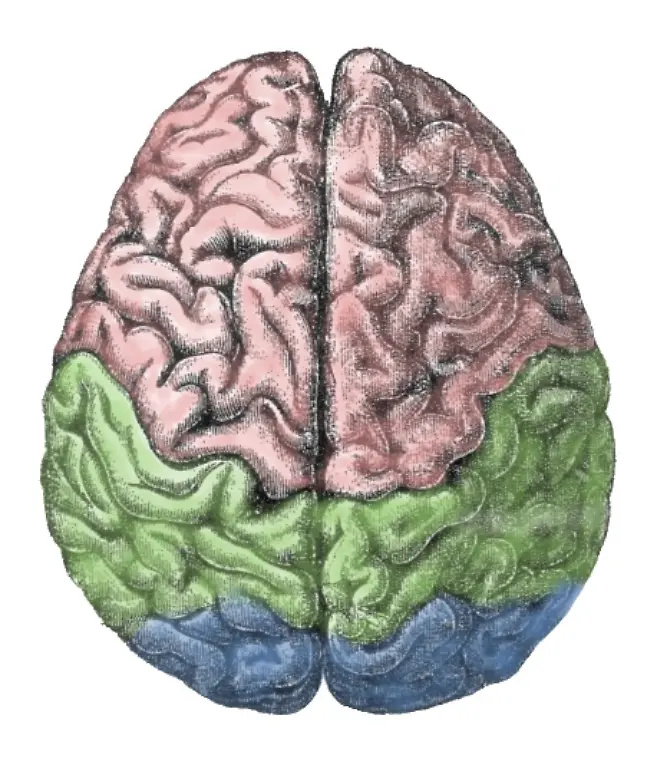

Egal, ob es ums Sehen oder Hören geht, ums Atmen, Sprechen, Rechnen oder Laufen: Stets sind es Milliarden grauer Zellen, die diese Fähigkeiten ermöglichen. Viele verschiedene Bereiche des Gehirns arbeiten zusammen, um die unterschiedlichsten Aufgaben zu lösen. Was wird von wo gesteuert? n-tv.de erklärt, was es mit Frontallappen, Mandelkern & Co. auf sich hat.